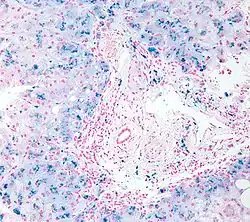

| Micrograph of liver biopsy showing iron deposits due to haemosiderosis. Iron stain. | |

Biopsy

The gold standard for confirming iron overload is the liver biopsy. Liver biopsy is the removal of a small sample in order to be studied and can determine the cause of inflammation or cirrhosis. In someone with negative HFE gene testing, elevated iron status for no other obvious reason, and a family history of liver disease, additional evaluation of liver iron concentration is indicated. In this case, diagnosis of hemochromatosis is based on biochemical analysis and histologic examination of a liver biopsy.